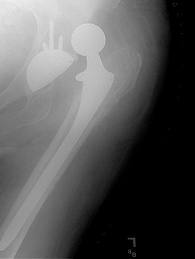

One man was even denied a hip replacement – although his hip was constantly dislocating.

NHS Oldham, which runs the Royal Oldham Hospital (pictured), hires nurses for its ‘referral management centres’

‘In one case, a patient was rejected for a replacement hip operation by a nurse at a referral centre despite the fact his hip was dislocating. According to the nurse’s criteria, he wasn’t reaching a high enough pain threshold because he already had an artificial hip that cured the pain.